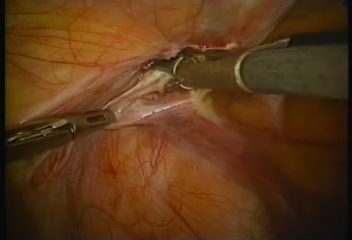

Intraperitoneal Inguinal Her..

Intraperitoneal Inguinal Her..

Morris E. Franklin, Jr., Jorge E. Balli / Cine-Med

Intraperitoneal Inguinal Her..

Intraperitoneal Inguinal Her..

Morris E. Franklin, Jr., Jorge E. Balli / Cine-Med